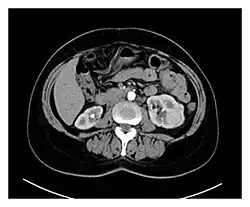

Preoperative contrasted CT scans of the patient, showing multiple bilateral kidney tumors, with diameters ranging between 1 and 5 cm. Radiologically, most of the tumors have malignant characteristics due to their hypervascularity and radiopaque enhancement.